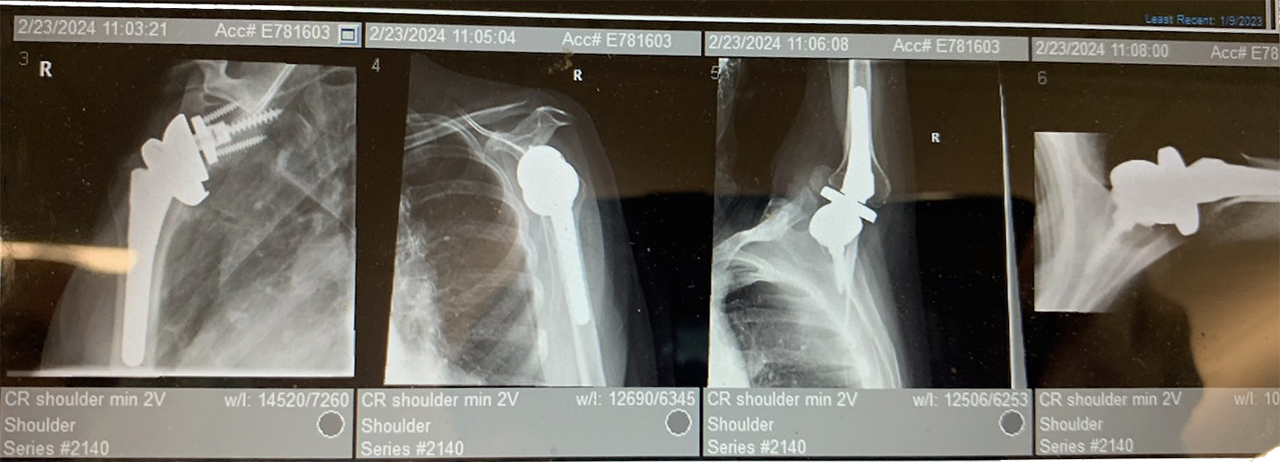

On November 30, 2023, Mary underwent her first surgery, performed by Dr. Jason Silva at Ortho Carolina, on her right shoulder.

With recovery going well, she had her 3-month follow-up x-ray. The x-ray technician ignored Mary 3 times when her range of motion was at its limit. They continued to move her arm higher and higher. This caused an immediate onset of pain.

On December 23, 2024, she was required to have revision surgery. Loose parts in her right shoulder were found and were replaced by another surgeon at another hospital.

Right shoulder x-rays of Mary Hunter